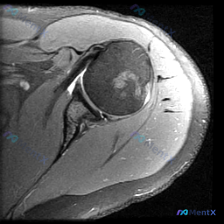

这个肩部MRI发现的肱骨头异常信号,更像良性还是恶性?

看到一个肩部MRI病例,先来看看影像核心信息: 基础资料:冠状位T2加权像,显示肱骨头、肩胛盂、肩峰、冈上肌腱等结构。 主要发现:肱骨头中部有不规则、边界相对清晰的混杂高信号区域,周围带低信号边缘。冈上肌腱连续,肩峰下间隙正常,肩峰形态尚可。 有人初步怀疑是「盂唇病变」,但仔细看,盂唇在冠状位显示有...